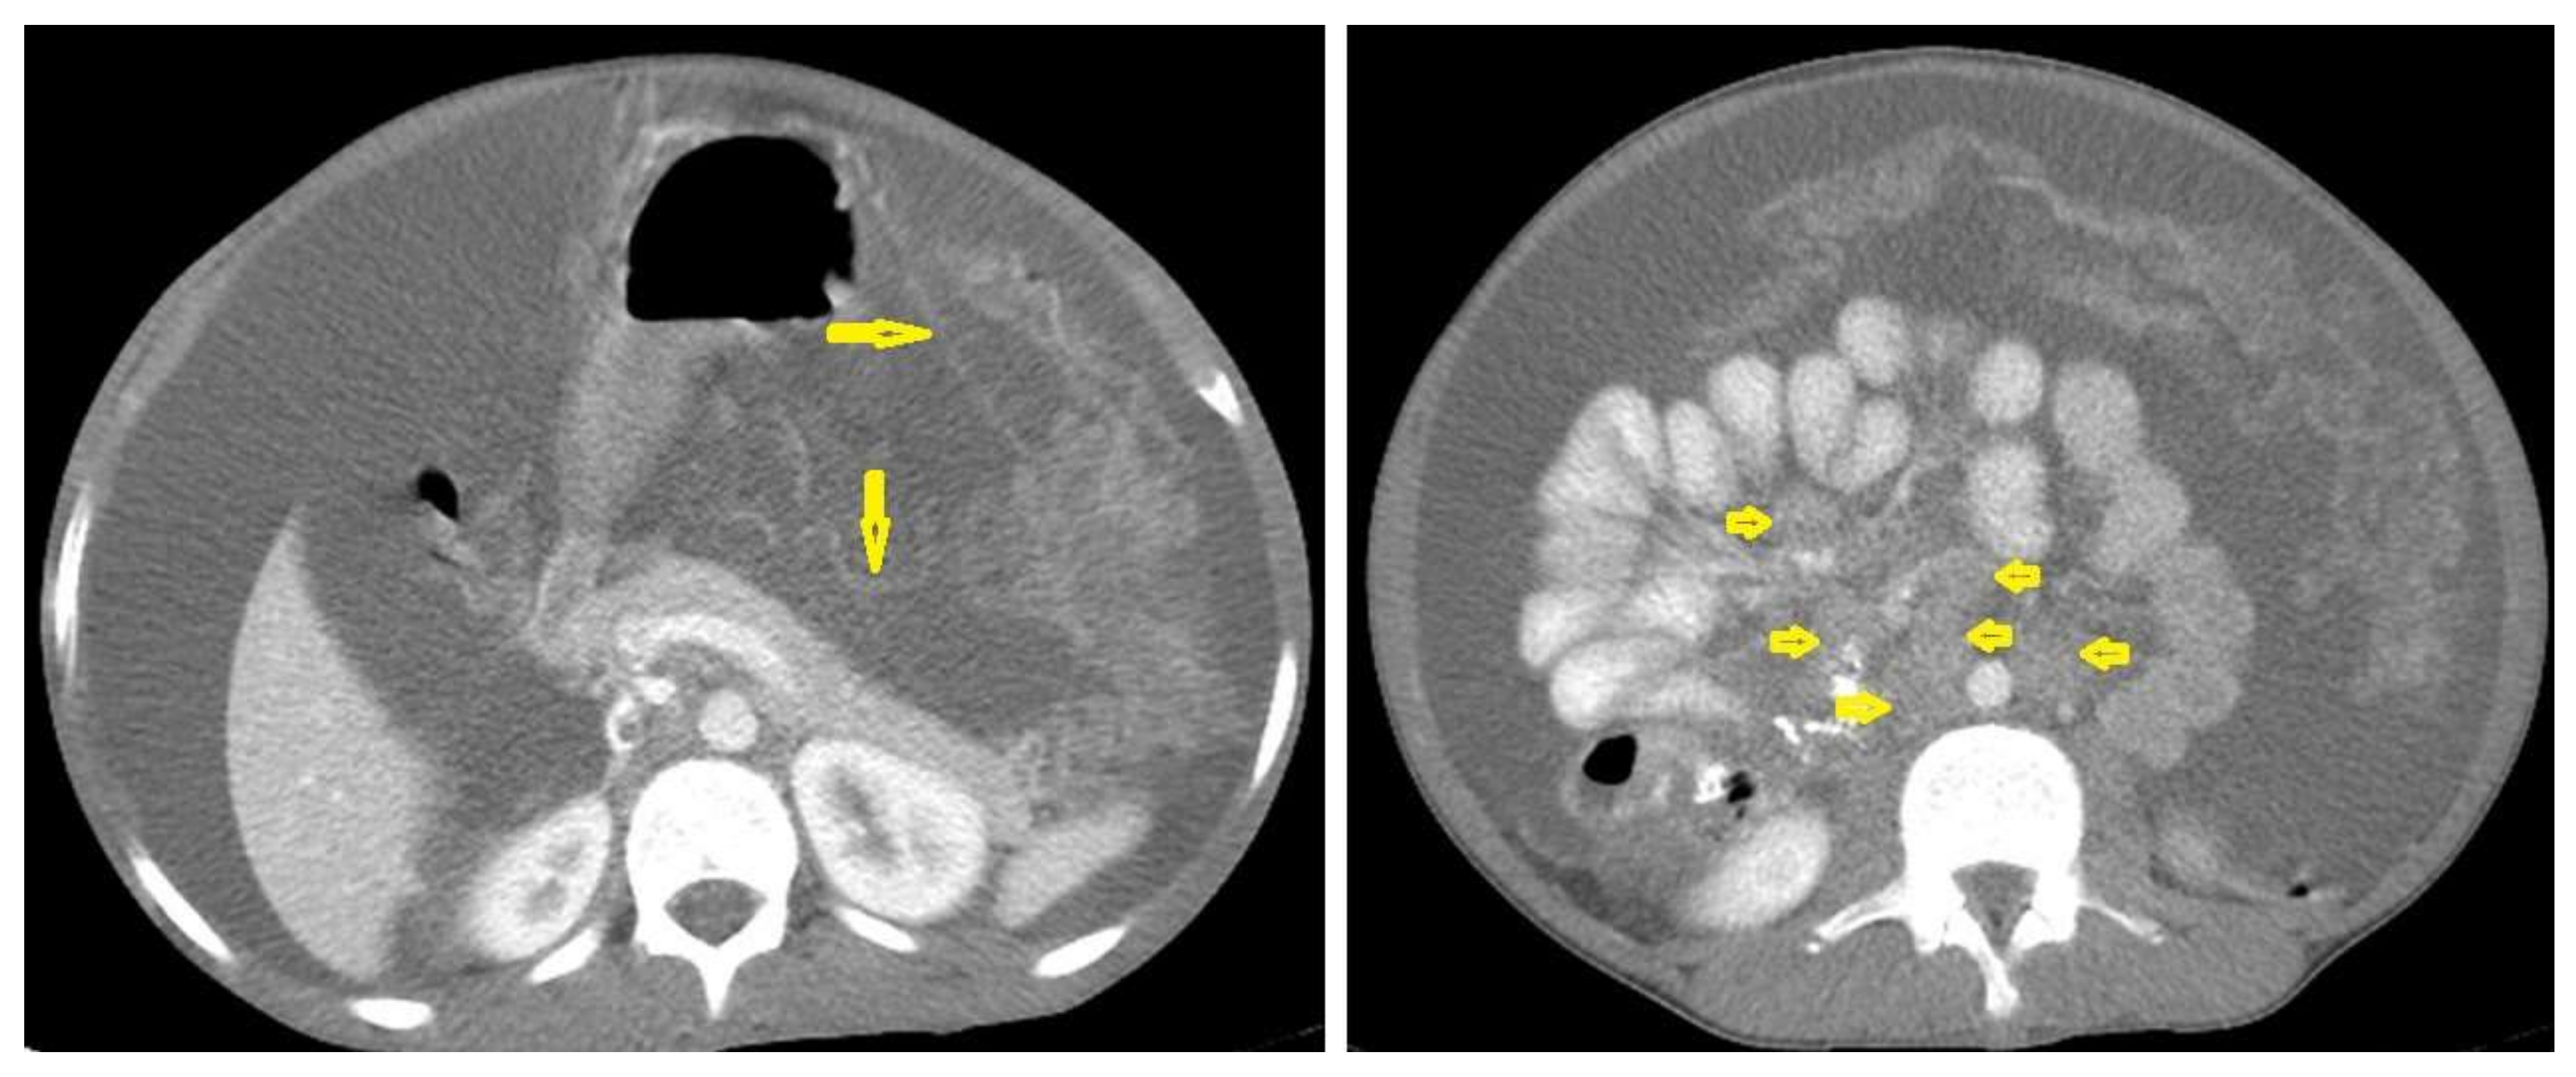

• Tuberculous lymphadenitis (Figure 20) is one of the most common radiological manifestation of abdominal TB which frequently involves multiple groups such as mesenteric and upper paraortic LNs. The majority of patients have enlarged lymph nodes with a low-attenuation center and peripheral-enhancing rim, which is characteristic of TB [45,46]. LNs may show peripheral rim enhancement, inhomogeneous, homogeneous, or no enhancement after contrast administration. Other patterns of LNs include conglomerate LNs with areas of necrosis, more than three enlarged or normal homogenous LNs in one section, or calcified LNs [45]. TB can mimic several other conditions, such as lymphoma, amebiasis, Crohn’s disease, and adenocarcinoma [47].

• Wet peritonitis (Figure 21) is the most common type that is characterized by free or loculated ascites with or without peritoneal thickening [46,47].

• Fibrotic peritonitis (Figure 22) is characterized by remarkable omental and mesenteric thickening forming cake-like masses with bowel loops enlargement and matting that can be seen by CT or ultrasound. [46,47].

Figure 20. Tuberculous lymphadenitis in a 27-year-old women with cachexia, loss of appetite and cough. Axial abdominal CT image shows enlarged mesenteric, periaortic, and portahepatis lymph nodes (LNs), (short arrows) due to TB, which usually involves multiple groups, such as mesenteric and upper paraortic LNs. The image also shows relatively dense ascites and remarkable omental thickening forming cake-like mass (long arrow).

Figure 21. Wet peritonitis in a 16-year-old man with cachexia and loss of appetite. Selected axial abdominal images show marked relatively dense ascites and gross thickened omentum with faint enhancement of peritoneal reflections (long arrows) with multiple enlarged mesenteric and upper paraortic conglomerated lymph nodes (short arrows) with slight homogeneous enhancement.

Figure 22. Fibrotic peritonitis in a 20-year-old man with fatigue, abdominal distension, and loss of appetite. Selected axial images of abdominal CT show remarkable omental thickening, forming cake-like masses (arrows) with faint enhancement and mild smooth thickening of peritoneal reflections associated with mild-to-moderate dense ascites and several low-attenuation mesenteric lymph nodes that are challenging to be distinguished from small bowel loops.